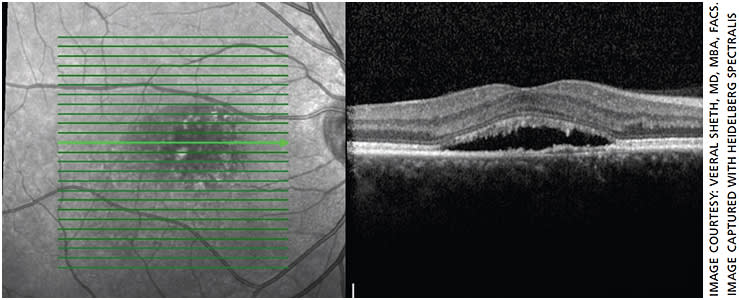

Similarly, Veeral Sheth, MD, MBA, FACS, partner & director of clinical trials, University Retina, with offices in the Chicago area, has used micropulse laser to treat patients with DME and CSCR (Figures 1-7). However, he notes, over the past decade he has used micropulse laser somewhat less for patients with DME and more for patients with CSCR. That’s because of the efficacy and safety profile of intravitreal injections for DME.

“The only quantification you have is when they follow up and you do an OCT and you see that there’s been improvement,” says Dr. Sheth.

One key to success is administering confluent treatment, notes Dr. Sheth. In traditional laser, he points out, you’re burning tissue and thus need to keep the spots fairly separated. With micropulse laser, “you’re able to actually cover an area more confluently and therefore treat more densely without the concern of burning or damaging tissue.”

“This dense or confluent treatment I think is critical,” he adds. “I think it’s something that physicians, especially early on with their use, don’t do, because they’re fearful, because it’s not traditionally how we do focal laser. The problem is, then you run the risk of not having optimal results. If you do a little bit more of this confluent type of treatment, you’re going to get better results.”